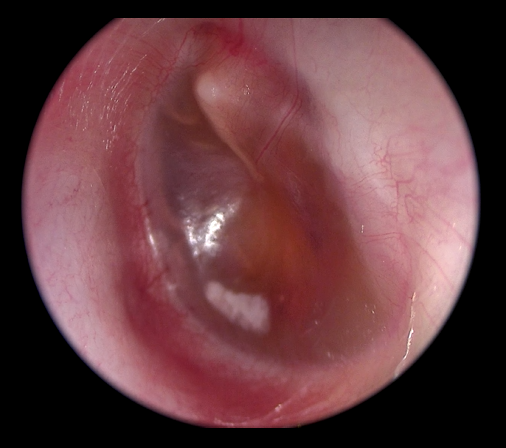

O diagnóstico da OME é feito no consultório durante o exame dos ouvidos. A otoscopia, exame físico dos ouvidos, revela um tímpano opaco, com presença de líquido visível atrás da membrana e, eventualmente, retraído e avermelhado. Em casos duvidosos, a timpanometria, é um exame essencial, pois mostra a mobilidade do tímpano. Resultados do tipo curva B (curva achatada) sugerem presença de acúmulo de líquido.